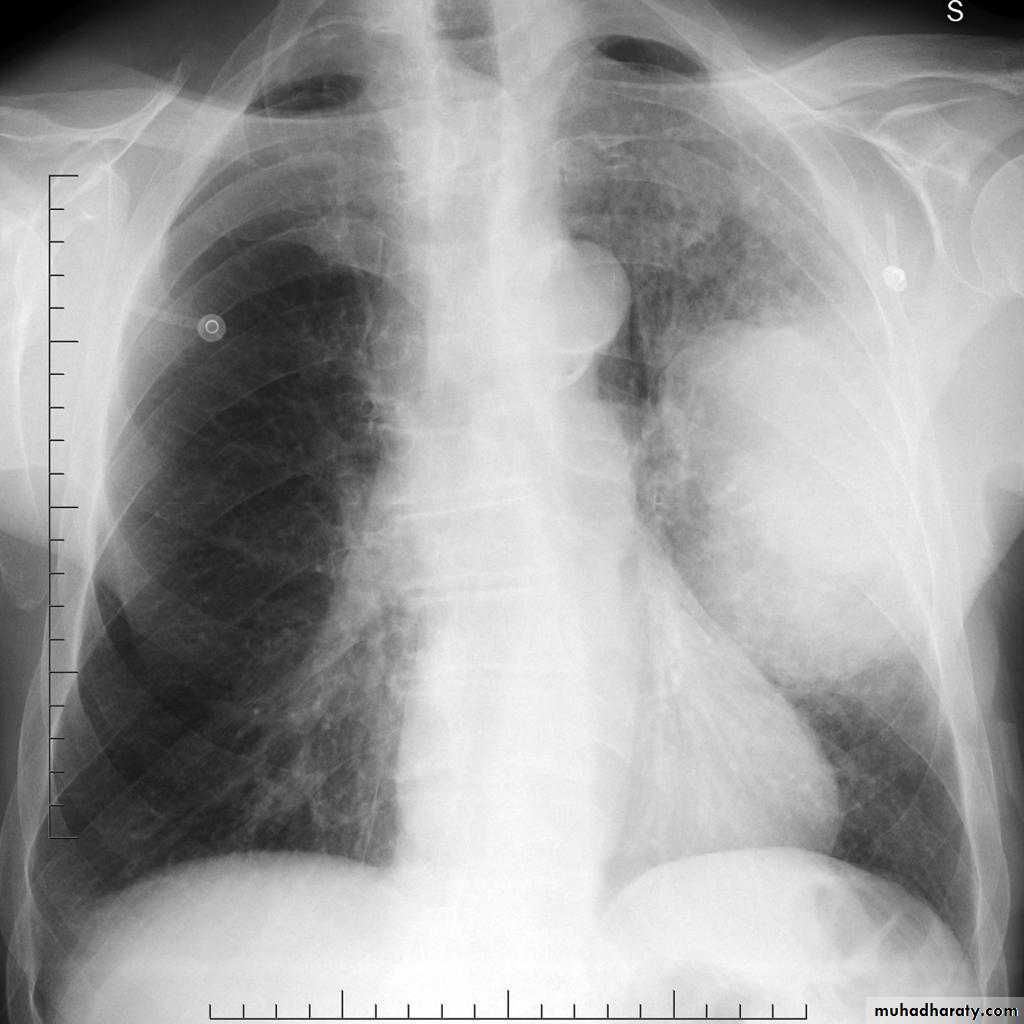

48.opasified hemi thorax

49.total collapse

Total collapse total consolidation

Total collapse